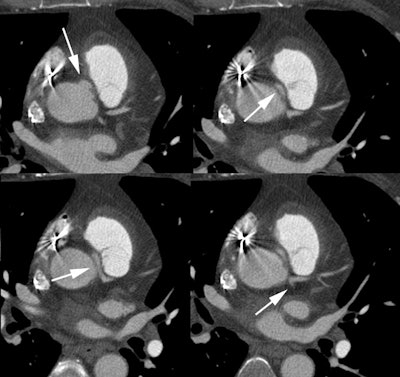

Anomalous LCA origin from the right coronary sinus: Coronary CT angiography was performed to assess for coronary artery disease. The patient was found to have an anomalous LCA arising from the right sinus of valsalva. The vessel can be seen to course between the pulmonary trunk and aorta (white arrows). Click the image to view the video clip. |